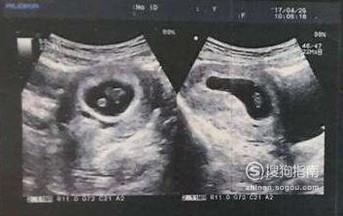

方法六:看B超孕囊的形状

在怀孕6周到8周准妈妈要进行第一次B超,以确定是否宫内好孕以及孕周。而孕囊的形状则被很多准妈们用来判断宝宝的性别,通常的说法是,如果孕囊是茄子状,或孕囊数据有一个是另外两个的两倍,那么就是男宝宝,如果孕囊是圆形,孕囊的三个数剧呈列比,那么就是女宝宝。这一条,我的两个宝贝都符合,但是根据其他宝妈们的反馈,也有例外的。